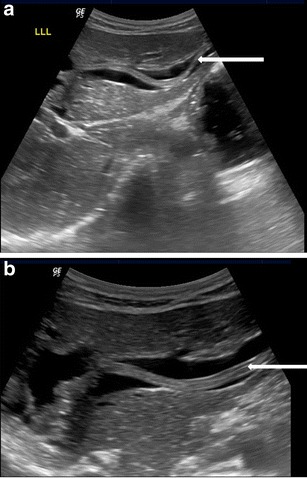

Gall bladder

Ascaris in the gallbladder is rare, constituting 2.1 % of hepatobiliary ascariasis [7]. This can be easily picked up on ultrasound. Inner tube may not be seen (Strip sign). Live worms may move within the gall bladder. The ascaris may be seen as a coil of worm in the gall bladder lumen (Fig. 7). The worm in the gall bladder may also present with cholecystitis (Fig. 8).

Fig. 7.

A 25-year-old female showing coil of ascariasis inside the gall bladder lumen (white arrow)

Fig. 8.

A 25-year-old male with acute right hypochondriac pain showing ascaris (thick white arrow) inside the gall bladder. Note GB wall thickening and luminal sludge indicating acute cholecystitis

Pancreatic duct

Rarely, ascaris in the main pancreatic duct can present with pancreatitis. The main pancreatic duct may be dilated, with “triple line sign”, “strip sign” or an “inner tube sign” and occasional pancreatic oedema (Fig. 9).

Fig. 9.

A 15-year-old male presented with acute epigastric pain and elevated pancreatic enzymes. High resolution ultrasound using linear array transducer shows ascaris with triple line within in the dilated main pancreatic duct (long white arrow) with pancreatitis